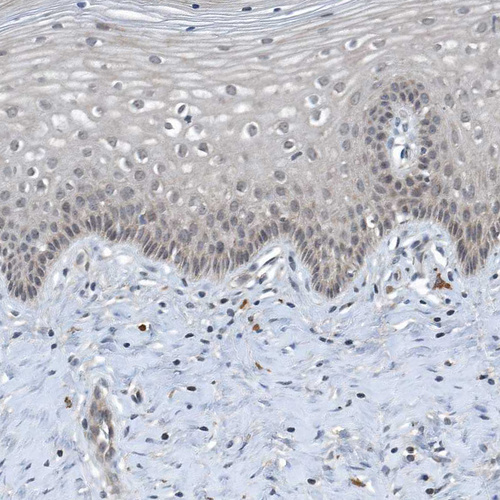

Immunohistochemical staining of human cerebral cortex, cervix, uterine, kidney and testis using Anti-SCFD2 antibody HPA036526 (A) shows similar protein distribution across tissues to independent antibody HPA036527 (B).